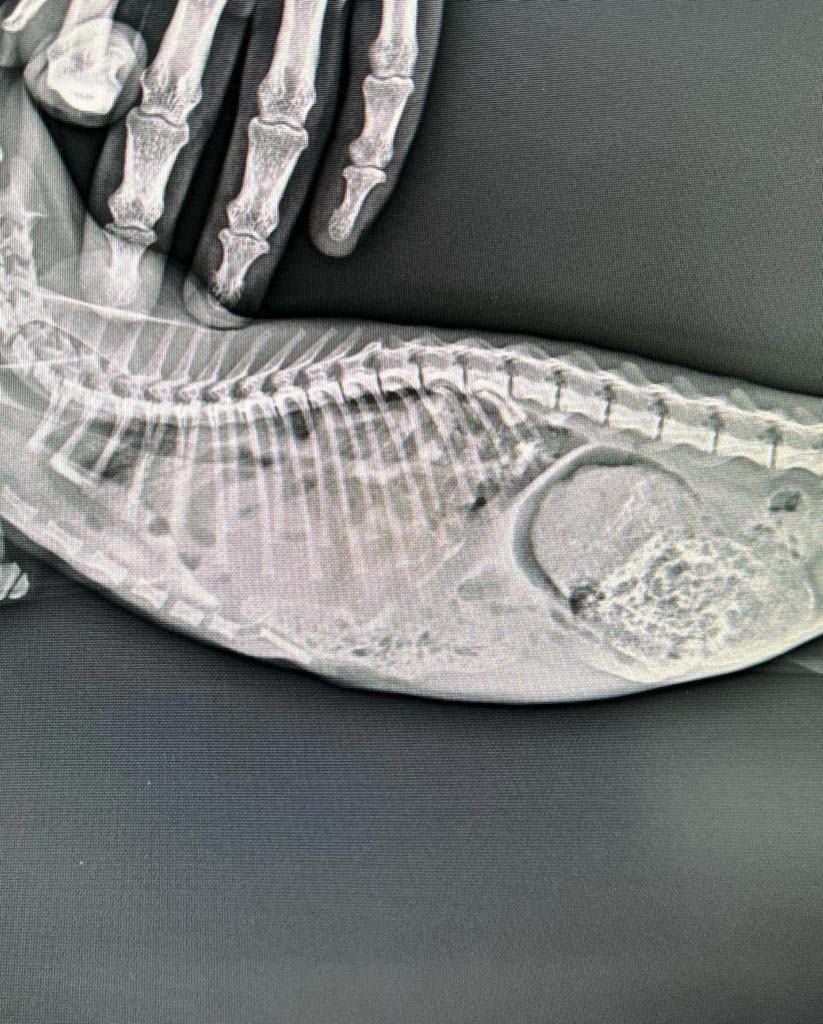

Veteriner hekim Gökmen Koç, muayene ettiği kedide doğumsal olarak diyafram zarında 5 santimetrelik bir yırtık tespit etti.

Veteriner hekim Gökmen Koç, “2 aylık sarman ırkı kedimiz, nefes alma sıkıntısı ile geliyor. Yapılan tetkiklerde karın organlarının akciğer ve göğüs boşluğuna deprese olduğunu anladık. Yapılan ilaçlı röntgenlerle aralıklarla röntgenler çekildi. Bağırsakların, midenin bir kısmının akciğerde gördük. Ardından ameliyat kararını verdik. Ertesi günde ameliyata aldık. Burada ki değişik olmasının sebebi de doğumsal olması. Hiç bir travmaya maruz kalmadan hastanın doğuştan gelen yırtığının olduğunu anladık. Diyafram zarında küçük bir yırtık değil bombeli bir yırtık olduğunu gördük. O yırtıkları ameliyatta da kanatarak diktik. Dokular canlansın diye. Çok şükür iyi geçti. Bugün dördüncü gün. Yaklaşık beşe beş cm bir yırtık vardı. Bu hayvan akciğer sadece ufacık bir yerden nefes alıyordu. Diğer loblar doluydu. İlerleyen zamanlarda üst solunum şikayetiyle hastayı kaybedebilirdik” dedi.